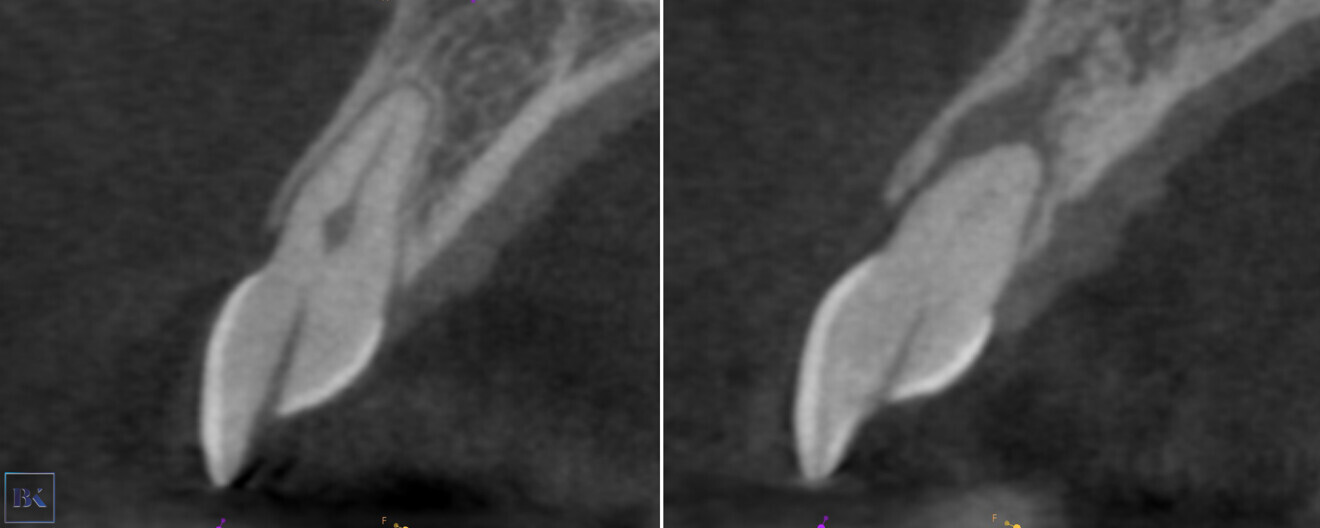

A 30-year-old female patient presented to the dental clinic complaining of constant pain of the left central incisor. Moreover, the patient was unhappy with the aesthetics of both incisors and had a history of trauma (Fig. 14). CBCT examination was performed with the 9000 C 3D (Fig. 15). The CBCT scan revealed a periapical lesion around the left central incisor and PCO for 12 mm from the incisal edge. The root of the left incisor was approximately 5 mm shorter than the root of the right incisor, which could indicate apical inflammatory root resorption. Moreover, PCO was present in the right central incisor up to 12 mm from the incisal edge, and an irregular shadow in the central area of the root was present. This image could indicate internal resorption. There was no lesion in the periapical area. In both teeth, the size of the canals in the periapical area were narrower than the typical size of the canals in the central incisors.

Figs. 15a–c: CBCT scan, sagittal (a & b) and coronal planes (c). Pulp canal obliteration was visible in both teeth, and a periapical lesion was present around the left incisor. Internal resorption in the right incisor was suspected.